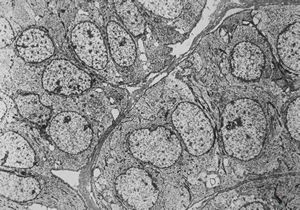

F, 85y. | Merkel cell tumor

F, 71y. | Merkel cell tumor